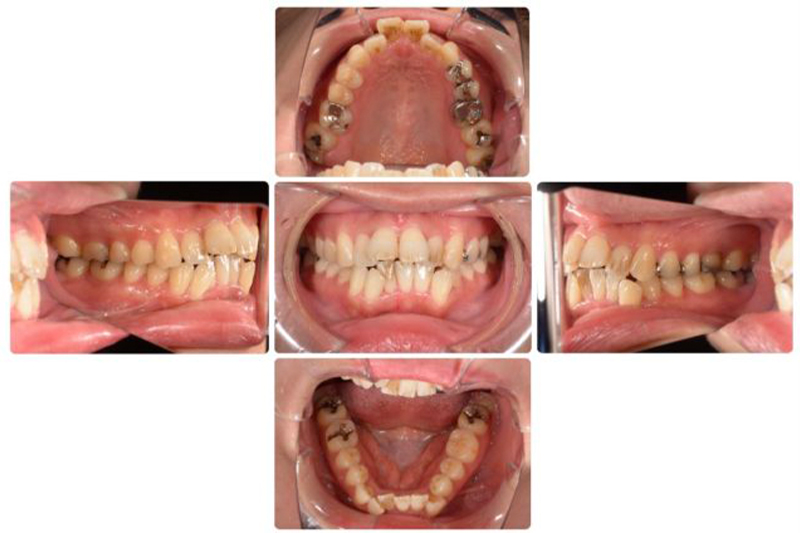

術前

術後

| 年代/性別 | 28歳/男性 |

|---|---|

| 主訴 | 歯並びを改善したい |

| 治療方法 | ワイヤー矯正による治療 |

| 費用 | 70万円 |

| 備考 | ワイヤー矯正のため、治療中の虫歯、歯周病の感染に対する対策が必要。 |

治療前は前歯の噛み合わせが悪く、奥歯へのダメージが危惧されたが、30代前半までに修正することができたので予後の安定を図ることができた。

患者さんも満足されていました。